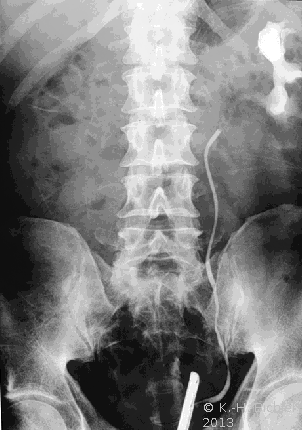

Die Diagnose wird mittels Anamnese (zystische Nierenerkrankungen in der Familie), RR-Messung, Labor (Kreatinin) mit genetischer Untersuchung, Sonographie, Computertomographie und gegebenfalls Kernspintomographie gestellt (Abbildung 4).

Ein i.v.-Pyelogramm kann im Rahmen der differentialdiagnostischen Abklärung des Flankenschmerzes indiziert sein (Abbildung). Sofern schon eine ausgeprägte Niereninsuffizienz vorliegt, sollte die Abklärung mit einem retrograden Pyelogramm erfolgen (Abbildung 5).